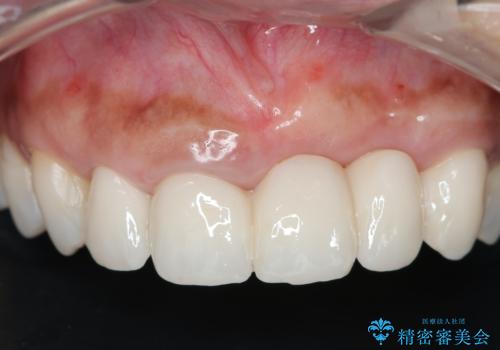

抜歯時に可及的に歯肉のボリュームを保つよう骨充填材とコラーゲン製剤による填塞を行い審美的かつ機能的なブリッジとなるよう治療を進めます。

- 66万円(ジルコニアクラウン×5・仮歯×5)費用は治療当時の料金となります

一件綺麗に見えるセラミックも適合や精度が悪いと、内部で虫歯が進行し亀裂や破折、悪臭の原因となることがあります。